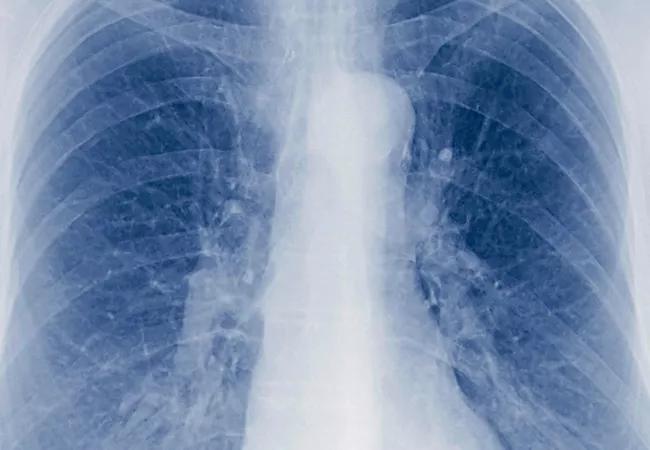

Non-Small Cell Lung Cancer Behaves Surprisingly Differently in Never-Smokers

Non-small cell lung cancer (NSCLC) — traditionally regarded as a disease of smokers — displays some key differences in patients who have never smoked, according to newly published data. Specifically, although never-smokers have better survival in stage I NSCLC than ever-smokers, they have more rapid disease recurrence and higher mortality in more advanced stages. Additionally, never-smoker NSCLC patients are more likely than their ever-smoker counterparts to be women, have disease in the lower lobe and have adenocarcinoma as the histopathologic subtype.